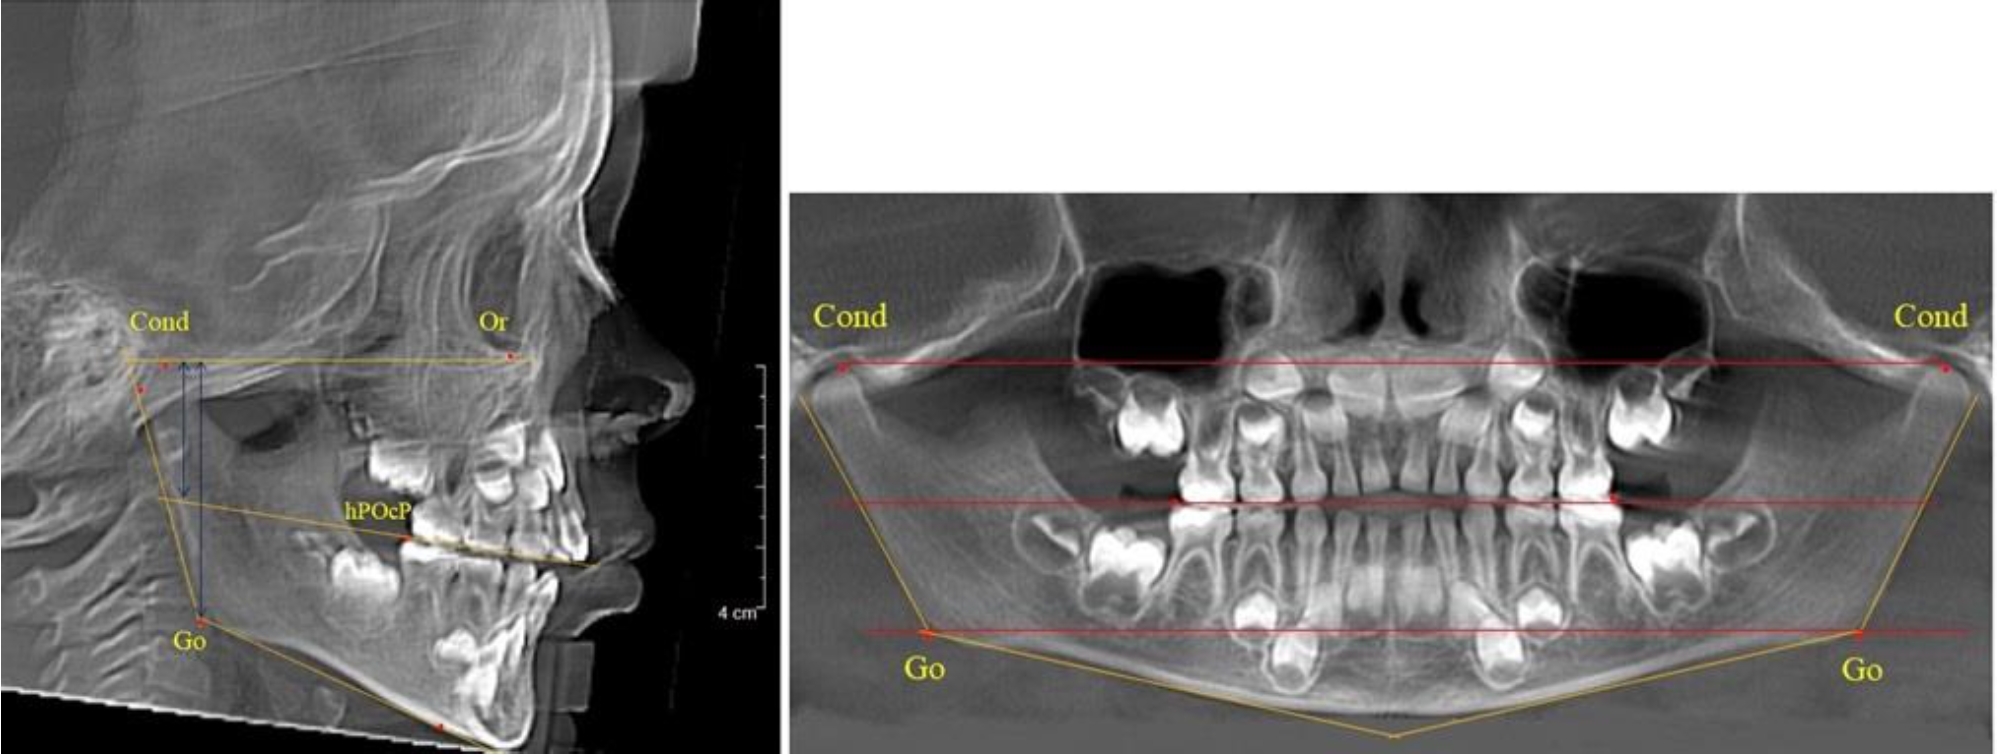

На боковых телерентгенгенограммах вершину суставной головки обозначали точкой кондиион Cond. Касательные линии к ветви и телу нижней челюсти пересекались в точке, которую обозначили Go. Точкой hPOcP обозначали дистальный бугорок нижнего второго моляра вблизи окклюзионного контура коронки. Указанный ориентир соединяли с межрезцовой точкой при построении окклюзионной линии. Высота ветви определялась расстоянием Go-Cond. Окклюзионная линия служила границей между верхней (окклюзионно-суставной) линией и нижней (окклюзионно-альвеолярной) линией.

На ортопантомограмме точки Cond соединяли между собой суставной линией Cond-Cond. Касательная к ветви нижней челюсти соединяла выступающие точки, которые соединялись в области угла и определяли положение точки гонион Go с обеих сторон, которые соединяли гониональной линией Go-Go.

Горизонтальная линя, соединяющая окклюзионные точки hPOcP, определялась как окклюзионная горизонталь.

В 1-й группе были проанализированы 7 телерентгенограмм и 7 ортопантомограмм, что составило (6,60 ± 2,41) % от числа изученных рентгенограмм. На всех парах рентгенограмм угол нижней челюсти, измеренный на телерентгенограмме, соответствовал углу, полученному при построении угла на ортопантомограмме. Окклюзионная линия практически однотипно делила ветвь на два отдела (рис. 1).

Как на ортопантомограмме, так и на телерентгенограмме высота ветви у детей в периоде сформированного прикуса молочных зубов составляла (42,21 ± 2,48) мм. При этом высота верхней окклюзионно-суставной части была (22,57 ± 1,46) мм, а нижней – (19,64 ± 1,54) мм.

Учитывая вариабельность абсолютных величин, определи относительные показатели соразмерности частей ветви нижней челюсти. Так, отношение высоты верхней части ветви к нижней в среднем составляло 1,15 ± 0,13. Отношение общей высоты ветви к верхней ее части составляло 1,87 ± 0,14, а отношение общей высоты ветви к нижней ее части было 2,14 ± 0,16 и достоверных различий по относительному показателю отношения всей высоты к верхней и нижней челюсти нами не отмечено (р ˃ 0,05). При этом визуально обе части выглядели примерно равноразмерными.

Рис. 1. ТРГ и ОПТГ пациента 1-й группы